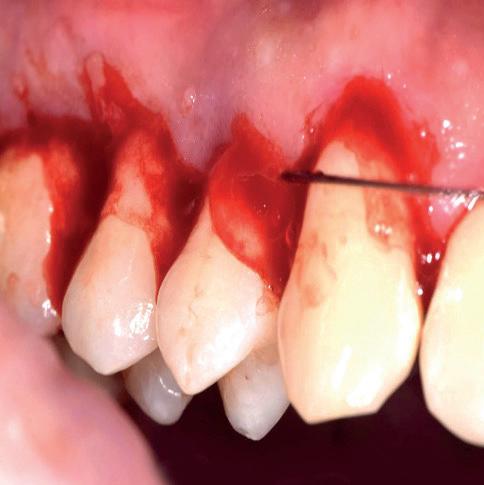

Een 62-jarige man hield in de nazorgfase een pocket van 8 mm met bloeding na sonderen mesiaal van de 36 ondanks 3-maandelijkse recall (afbeelding 2.1 en 2.3). De mondhygiëne was matig en plaque was aanwezig. Chirurgie werd geadviseerd, maar de pa-

tiënt wees dit af. Ook hier werd de pocket behandeld onder anaesthesie. De natriumhypochloriet/aminozuur-gel werd viermaal aangebracht, telkens gevolgd door ultrasone en handinstrumentatie. Tot slot werd cross-linked hyaluronzuur ingebracht. De mondhygiëne werd bijgestuurd en meneer werd gemotiveerd dagelijks interdentale ragers te gebruiken naast het poetsen.

Na zes maanden was de pocketdiepte teruggebracht tot 3 mm en was er geen bloeding na sonderen (afbeelding 2.2 en 2.4).